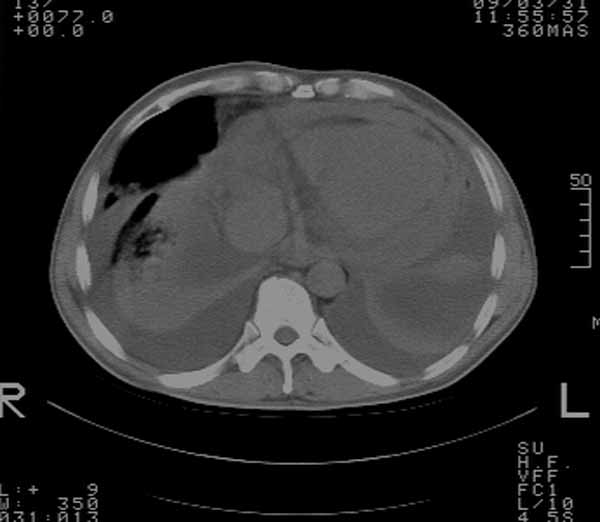

以下是引用余辉在2009-3-31 18:43:00的发言:[br]肺水肿,双侧心腔积液,心包积液,心影增大,疑似心衰

以下是引用wangyong1977在2009-3-31 20:46:00的发言:[br]肺水肿,双侧胸腔积液,心包积液,心影增大,疑似心衰 [br]

以下是引用宇宙ct在2009-3-31 18:57:00的发言:[br]肺水肿,双侧心腔积液,心包积液,心影增大,疑似心衰 [br] [br]